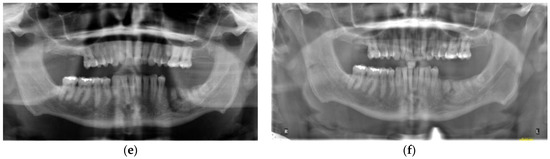

3.2. Case 2